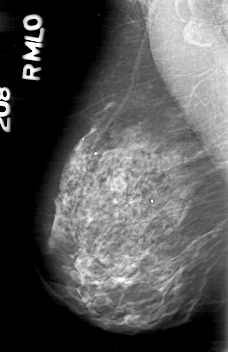

D_4164_1.RIGHT_MLO

D_4164_1.RIGHT_CC

RIGHT_CC LINES 5236 PIXELS_PER_LINE 3346 BITS_PER_PIXEL 12 RESOLUTION 43.5 NON_OVERLAY

RIGHT_MLO LINES 5266 PIXELS_PER_LINE 3406 BITS_PER_PIXEL 12 RESOLUTION 43.5 NON_OVERLAY